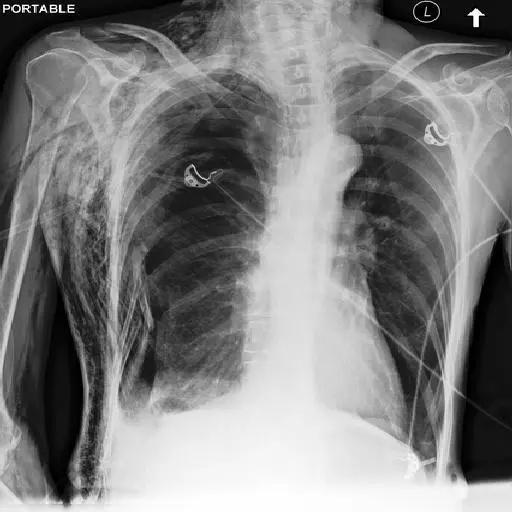

Cogninn is collaboration with university hospitals and private health centers develops custom AI solutions for image to text applications for clinical diagnosis applications.